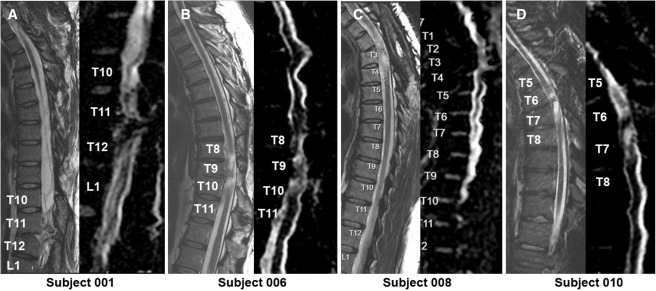

本次發(fā)布的I期臨床研究旨在評(píng)估神經(jīng)干細(xì)胞移植治療慢性胸椎脊髓損傷的安全性和初步療效。研究選取了四名完全性ASIA-A級(jí)胸部SCI患者作為受試者,這些患者的損傷時(shí)間均超過一年,且在接受任何其他形式的有效治療后仍未見明顯好轉(zhuǎn)。

每位受試者接受了每個(gè)注射點(diǎn)含有2×105個(gè)神經(jīng)干細(xì)胞,通過定制的立體定向設(shè)備,雙側(cè)注入損傷部位周圍的剩余組織及下方約一個(gè)節(jié)段的內(nèi)側(cè)白質(zhì)區(qū),整個(gè)過程由術(shù)中熒光透視成像指導(dǎo)完成。

4.影像學(xué)評(píng)估:術(shù)后MRI顯示所有患者存在不同程度的局灶性脊髓軟化,但未見新的并發(fā)影像學(xué)征象(如水腫、增強(qiáng)或積液);DTI提示脊髓束外觀穩(wěn)定,未見廣泛重塑或纖維束改善。

MRI頸胸T2矢狀圖和AvDC矢狀圖